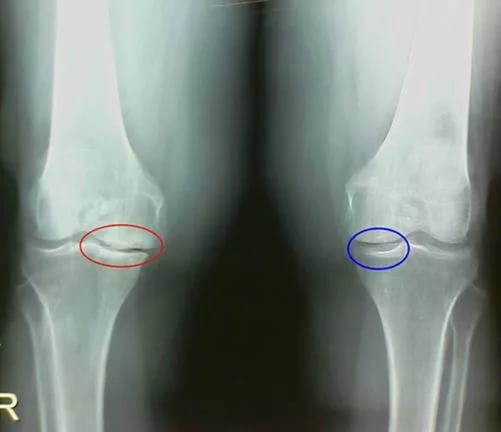

Учитывая, что коленный сустав постоянно подвержен большим двигательным нагрузкам, нехватка синовиальной жидкости в его полости чаще приводит к повреждению хрящей суставных поверхностей. Хрящевая ткань не имеет кровеносных сосудов, поэтому все полезные микроэлементы она получает из синовиальной жидкости.